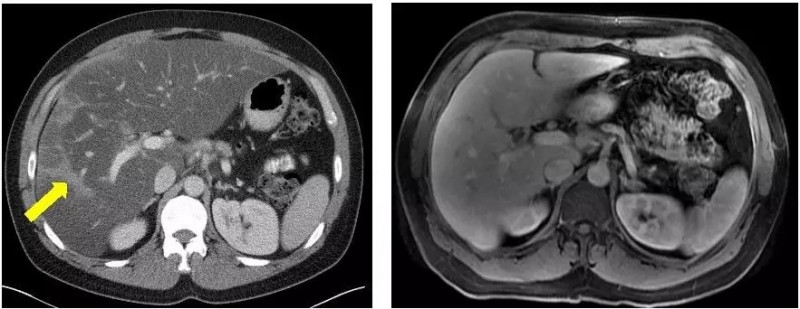

确诊时

在接受最强的化疗方案FOLFIRINOX后,肿瘤虽然缩小,但是他无法承受强烈的副作用。他的主治医生,丹娜法伯癌症研究院的Kimmie Ng博士检测了Broman的肿瘤DNA的全部外显子序列,显示BRCA2基因的突变。他的医疗团队决定使用靶向Brac突变的药物,称为PARP抑制剂的olaparib(Lynparza) ,尽管这款药物当时仅获批用于卵巢癌。

在他使用奥拉帕尼六个月后,MRI和CT扫描显示没有癌症复发,生物标志物水平保持在正常范围。Ng说,只要癌症得到控制,他可以无限期地服用奥拉巴利,因为副作用很小。

FOLFIRINOX治疗5个月病灶明显缩小 vs olaparib治疗21个月病灶全部消失